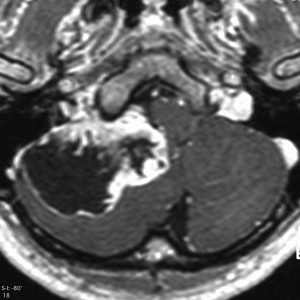

症例:頸静脈孔から頭蓋内へのもの

頸静脈孔を中心に頭蓋底骨の破壊 erosionがみられます。小脳延髄角部に進展して延髄を圧迫しています。聴神経を圧迫して聴力低下で発見された,迷走神経鞘腫です。頸静脈孔内発生のものは脳槽内の迷走神経根から腫瘍を剥離することができます。

手術直後のMRIです。頸静脈孔より深い位置にある腫瘍まで摘出しようとすると,舌咽,迷走,副神経を損傷しますから,最深部の部分だけ残して摘出しました。

手術後14年が経過しますが,無治療で残存腫瘍は縮小しました。術後神経鞘腫の自然経過ではよく観られることです。